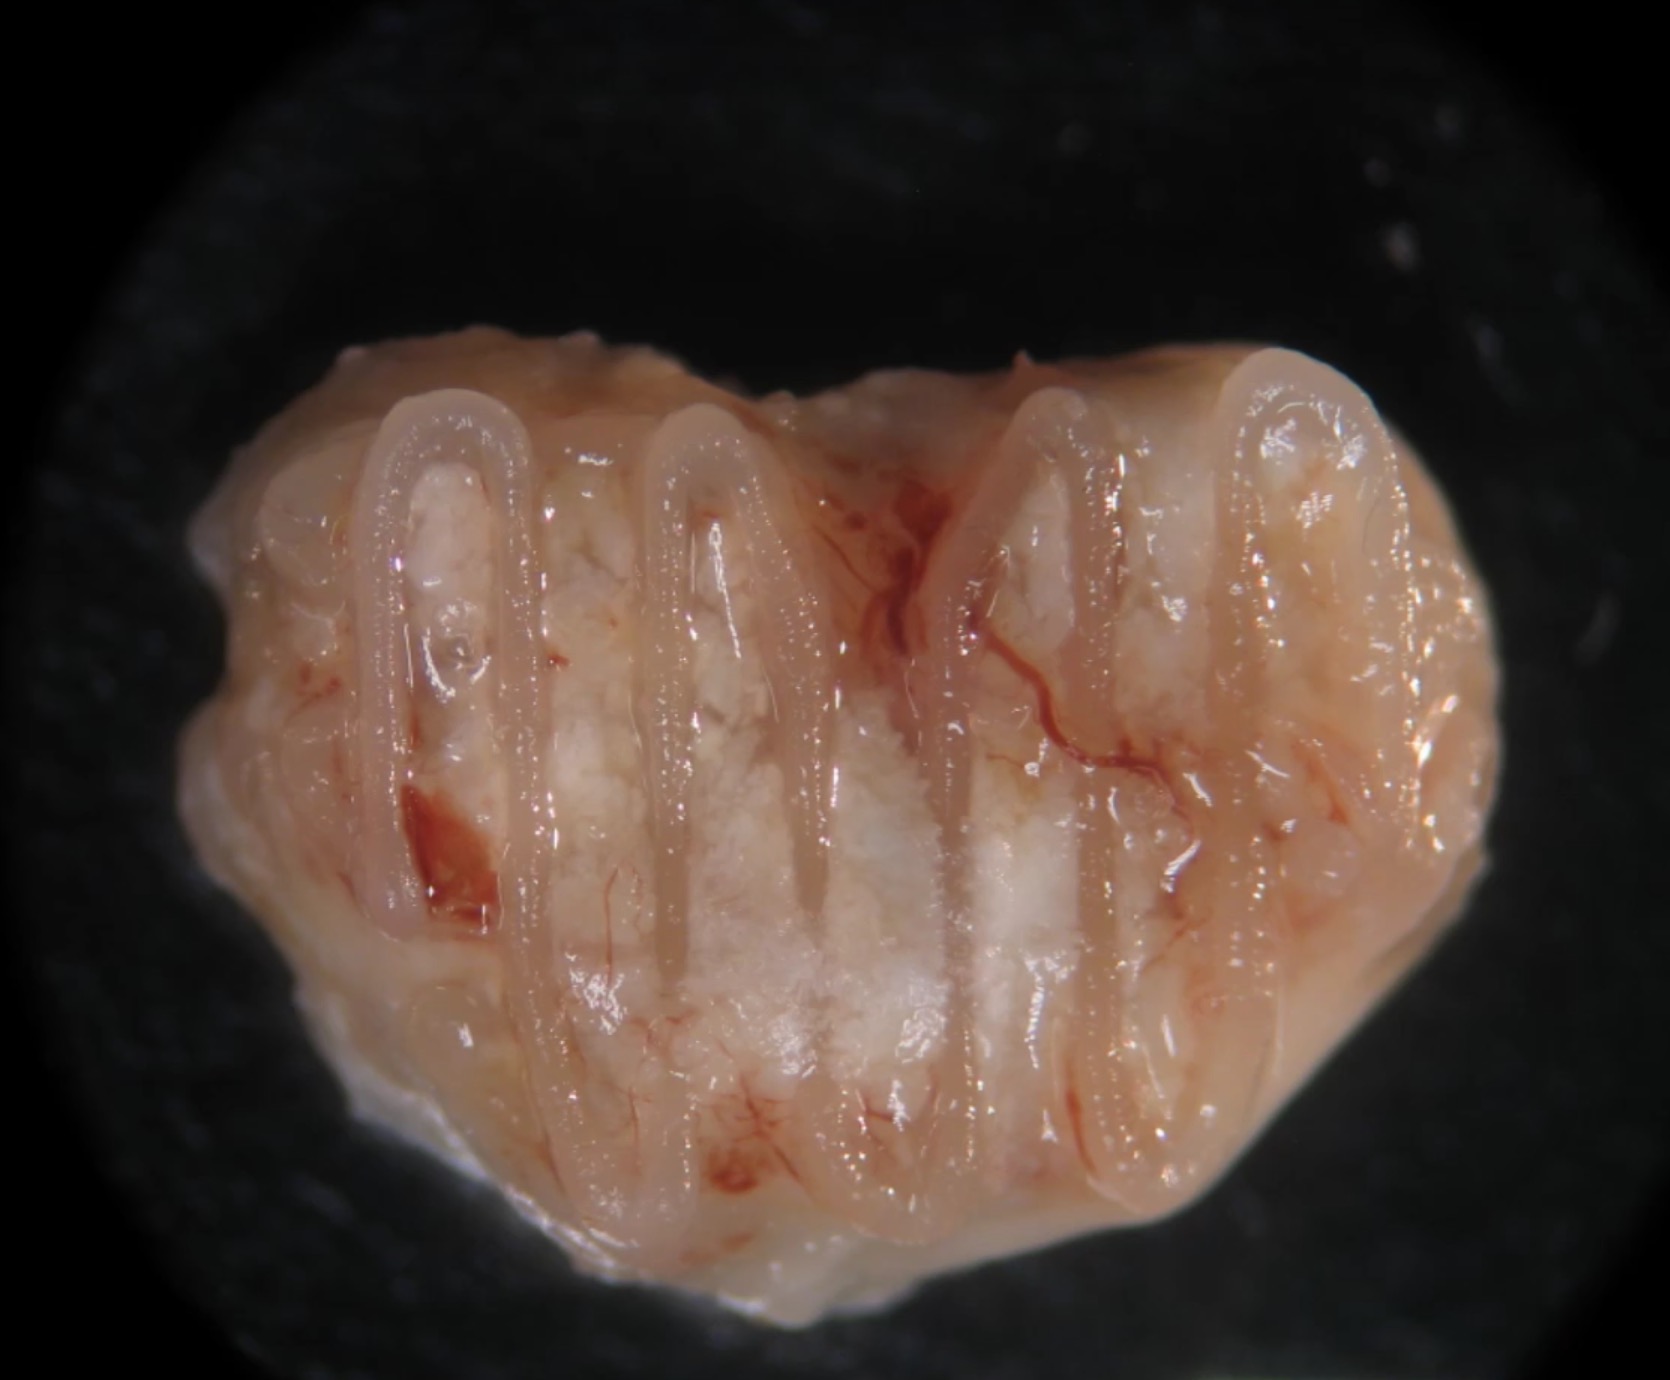

BioPrinting Breakthrough in Ireland

Researchers at Trinity College in Dublin have worked out a new process for 3D printing live, complex bone structures.